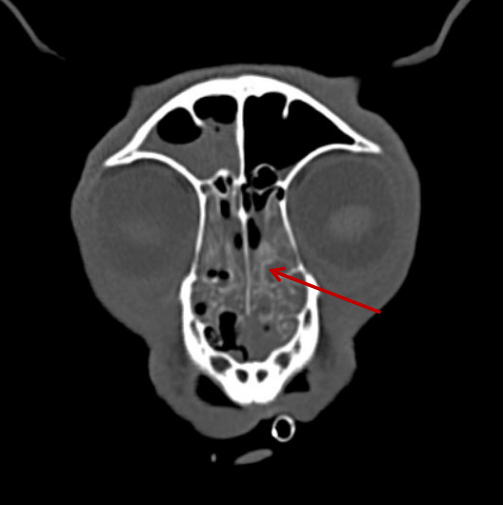

111.png

▲相比之下,這只狗狗的鼻竇炎可算是小毛病了。